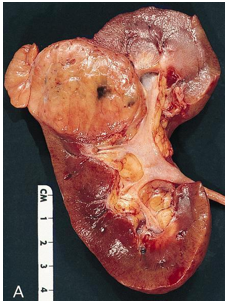

Hình 3. ccRCC có màu vàng, giới hạn ở thận (pT1b)

Đại thể

Thường là khối u vỏ thận một bên và đơn ổ, kích thước trung bình khoảng 7 cm. Khối u thường có ranh giới rõ, được bao quanh bởi giả bao u, phát triển theo kiểu đẩy nở và lồi ra từ vỏ thận. Hình thái đại thể đa dạng với thành phần đặc và nang, kèm các vùng xơ hóa màu xám và các ổ xuất huyết mới hoặc cũ màu nâu; hoại tử và biến đổi nang gặp thường xuyên. Khối u có màu vàng ánh kim do hàm lượng lipid cao; các khối u có độ mô học cao hơn có thể không có màu vàng do hàm lượng lipid và glycogen thấp hơn. Các vùng mềm, dạng thịt có thể phản ánh sự hiện diện của biệt hóa dạng sarcomatoid. Thường xuyên ghi nhận xâm lấn tĩnh mạch thận và xoang thận. Tổn thương hai bên và đa ổ là đặc điểm gợi ý bệnh lý di truyền.

Hình 4. ccRCC đa ổ, với diện cắt đại thể loang lổ,khối u màu vàng óng xen kẽ các vùng xơ hóa và xuất huyết. Các vùng mềm, dạng thịt, màu nâu nhạt đến trắng xám trong khối u có thể gợi ý sự biệt hóa sarcomatoid.